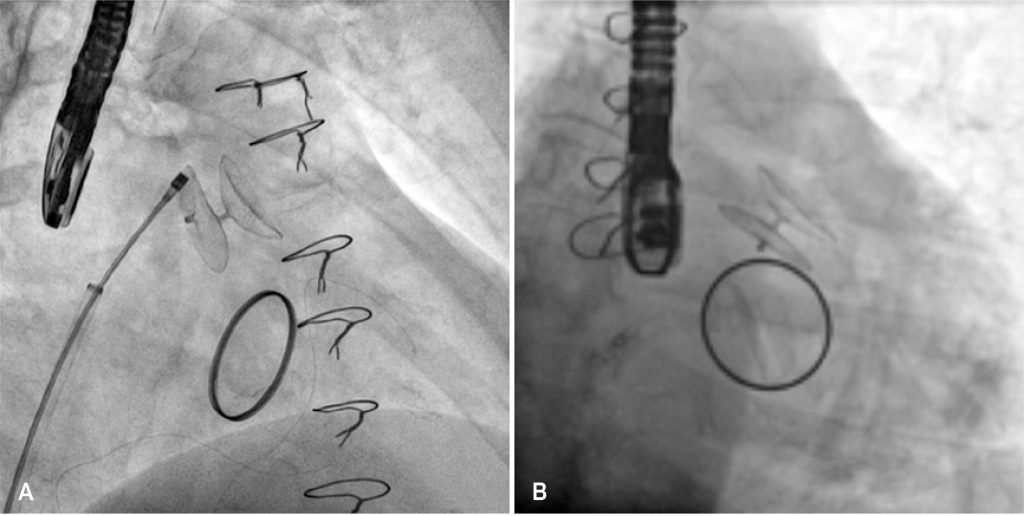

Figura 2

Implantação do dispositivo. (A) Dispositivo totalmente configurado, ainda conectado ao sistema de liberação por uma alça de fio de nitinol. (B) Dispositivo totalmente desconectado do sistema de liberação.